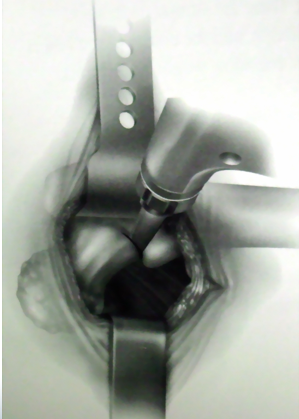

沿阔筋膜纤维方向切开扩筋膜大粗隆顶点臀中肌前1/3处沿纤维方向分离臀中肌

横形切开臀小肌2cm

沿大粗隆前缘切开臀中肌腱和臀小肌

切除关节囊髋关节内收、屈曲、外旋位脱位

准备髋臼

准备股骨髓腔

缝合切开之臀小肌和臀中肌